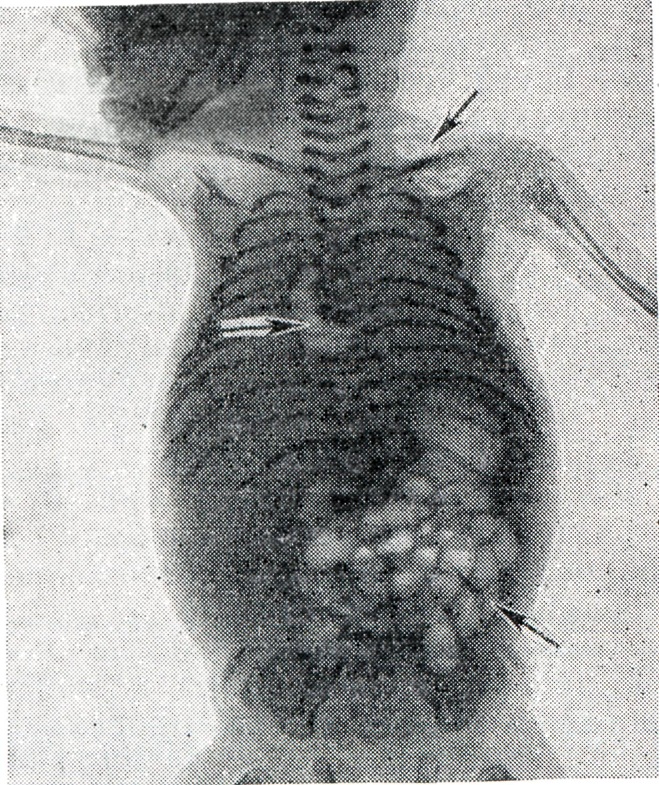

Костный скелет плода при Внутриутробная смерть характеризуется изменившимся по сравнению с нормой положением отдельных частей скелета и неправильными взаимоотношениями костей черепа, позвоночника и конечностей; в костях черепа происходят такие изменения, как черепицеобразное захождение краёв костей друг за друга (рисунок 1), уменьшение вследствие этого размеров черепа, расхождение костей со ступенчатым смещением одной кости по отношению к соседним, деформация черепа (уплощение свода или мешкообразная вытянутость формы).

Рис. 1.

Резкое смещение теменной кости вниз и вперёд (указано стрелкой) при внутриутробной смерти плода; рентгенограмма.

Изредка наблюдается резко выраженная поротичность костей и отвисание нижней челюсти. Изменение соотношений черепа с позвоночником может проявиться в ненормальном отклонении головки. В позвоночнике наблюдается выпрямление его продольной оси, а иногда чрезмерный лордоз или, наоборот, угловой кифоз. Признаком Внутриутробная смерть служит также необычное, беспорядочное расположение конечностей, не соответствующее так называемый утробному положению плода.

Выявление газа в полостях сердца плода всегда затруднительно из-за наличия газов в кишечнике матери, но газ без труда обнаруживается при рентгенографии мертворождённого. Присутствие газовых скоплений в сердце и крупных сосудах объясняют посмертным внеутробным гниением в том случае, если уже имеются значительно выраженные наружные признаки трупного разложения, когда газы скапливаются и в подкожной клетчатке (рисунок 2).

Рис. 2.

Гнилостный газ (указан стрелками) в подкожной клетчатке левого плечевого пояса, в сердце и в желудочно-кишечном тракте мертворождённого, образовавшийся внутриутробно; рентгенограмма,